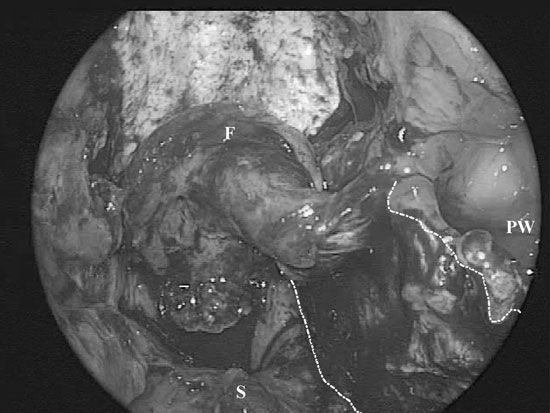

Figura 2C.

c) Intraoperative photograph of the repair. A black line has been added to highlight the edges of the flap.